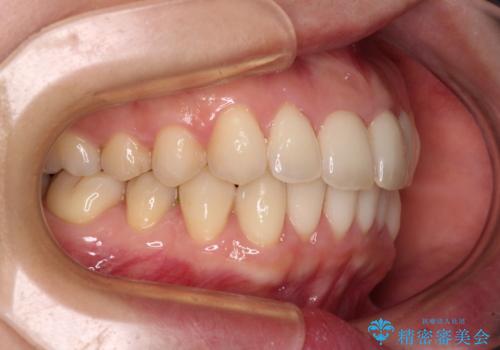

出産をしながら歯列を整える インビザラインによる矯正治療

- 上下の前歯のデコボコを気にして来院された患者様です。

妊娠中であり、途中通院が難しくなる可能性があることから、インビザラインによる矯正治療を行うこととしました。

上下顎歯列全体の後方移動とIPR(歯と歯の間を削る)によってデコボコが解消するように設計しました。